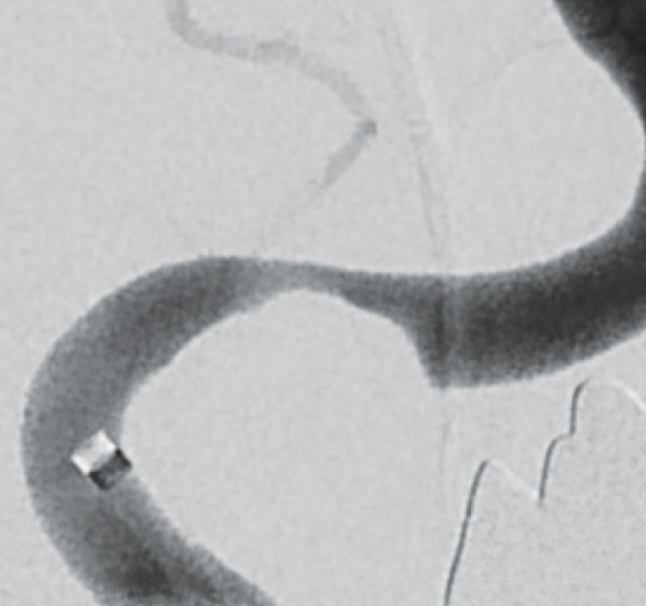

Pre-interventional diagnostic stenosis grade 80 %

Deployment of CREDO® Stent after pre dilation with NeuroSpeed® PTA Balloon Catheter

Final control after stent placement stenosis grade 30%